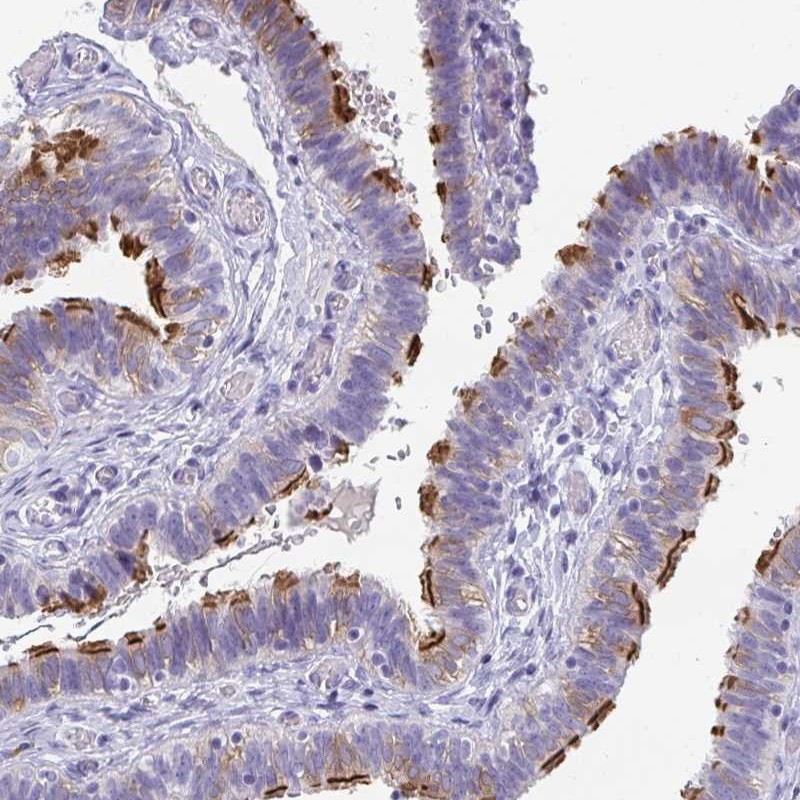

Immunohistochemical staining of human fallopian tube shows distinct positivity in cilia.